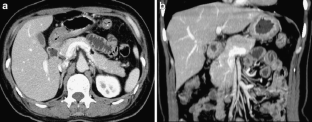

Fig. 1